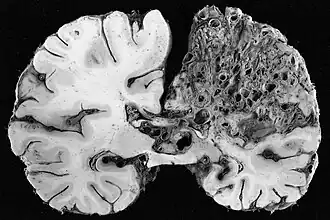

- angiome caverneux (ou « cavernome cérébral ») ; malformation vasculaire située en grande partie dans le cerveau, généralement non détectée, sauf lorsqu'elle cause des crises convulsives ou des hémorragies cérébrales (fréquence : 1 sujet sur 1 000, avec forme familiale dans 20 % des cas). Trois gènes situés sur les chromosomes 7 et 3 semblent impliqués ;